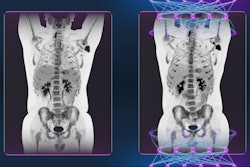

A PET/CT radiomics model based on imaging with a gallium-68 (Ga-68) PSMA-11 radiotracer could help clinicians diagnose primary prostate cancer, according to a study by Chinese researchers published September 30 in EJNMMI Research.

A group at Nanjing Medical University in Nanjing developed an algorithm based on features from Ga-68 PSMA-11 PET/CT scans of patients diagnosed with proven prostate cancer or benign prostate disease. In testing, the model outperformed visual assessments by nuclear medicine radiologists.

Still, significant numbers of intraprostatic lesions can be missed by visual PET image interpretation due to their small size or configuration. In this study, the researchers hypothesized that a radiomics approach based on quantitative measures of PSMA expression may fill this diagnostic gap.